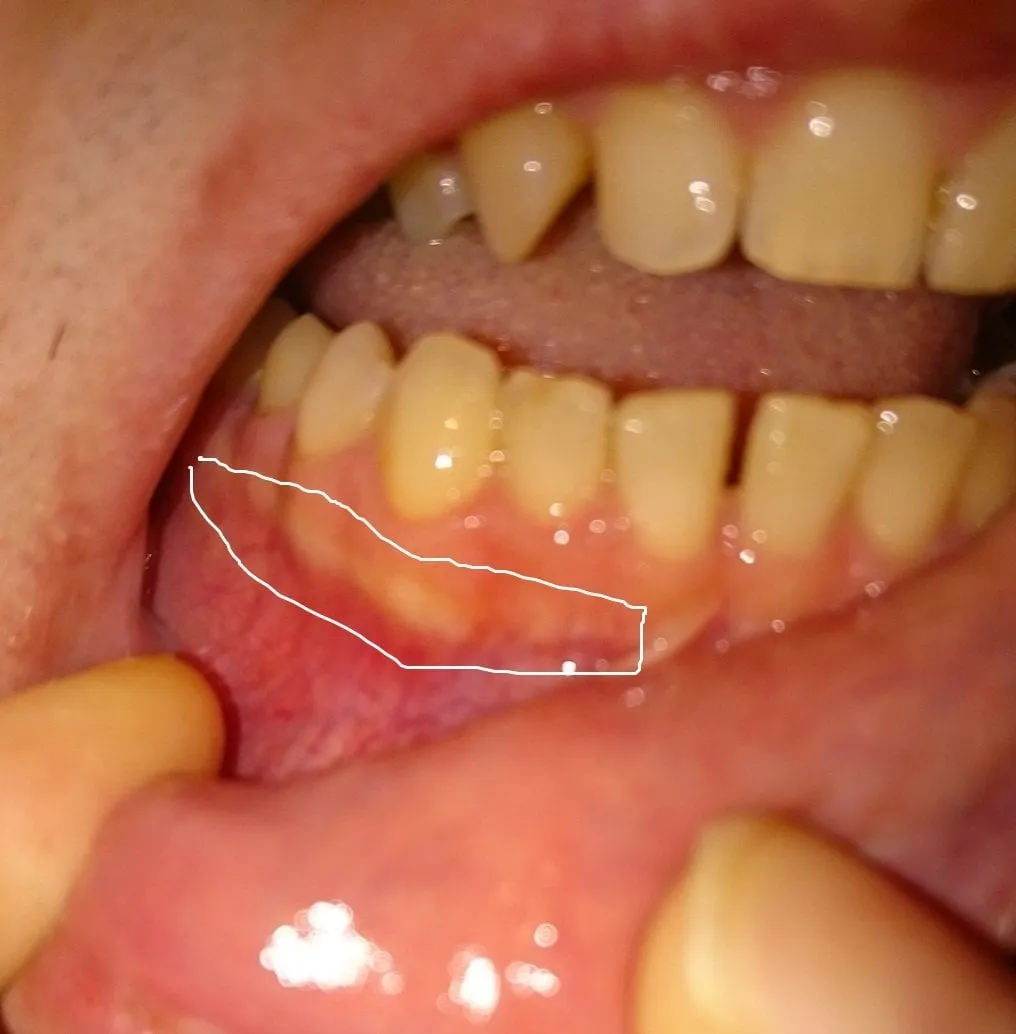

When to Seek Professional Help

While many cases of white spots resolve on their own, knowing when to seek professional help is important. If you experience persistent white spots or any signs of gum irritation, such as redness, swelling, or bleeding, consult your dentist. They can assess the condition of your gums and determine the appropriate course of action. A dentist can provide treatments to address any issues, such as desensitizing agents, anti-inflammatory medications, or other remedies to promote gum healing. If the white spots are severe or accompanied by pain, professional intervention is necessary. Do not hesitate to seek professional help if you have concerns about your oral health. Early intervention can prevent complications and ensure your comfort and well-being. Your dentist can provide the care you need.